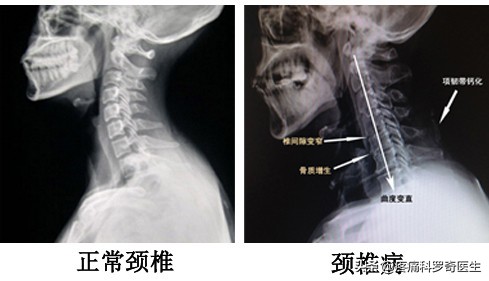

颈椎退行性改变,颈椎曲度变直

颈椎内热针软组织松解治疗